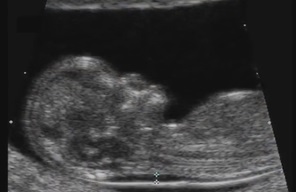

Sarcina dupa 35 de ani: riscuri si metode prin care le prevenim

Multe dintre femei aleg sa amane o sarcina pana dupa 30 de ani, ca urmare a dorintei de a-si construi o cariera stabila. Aceasta pentru ca isi doresc stabilitate si siguranta financiara. Asadar, in ultimii ani a crescut numarul de sarcini dupa 35 de ani. De aceea, este important a cunoaste care sunt provocarile unei astfel de sarcini si cum pot fi acestea depasite.

Teste si controale necesare in cazul unei sarcini peste 35 de ani

In cazul unei mame de peste 35 de ani, pentru monitorizarea sarcinii sunt esentiale unele teste si investigatii. Astfel, in cadrul examenului clinic al mamei se urmaresc: